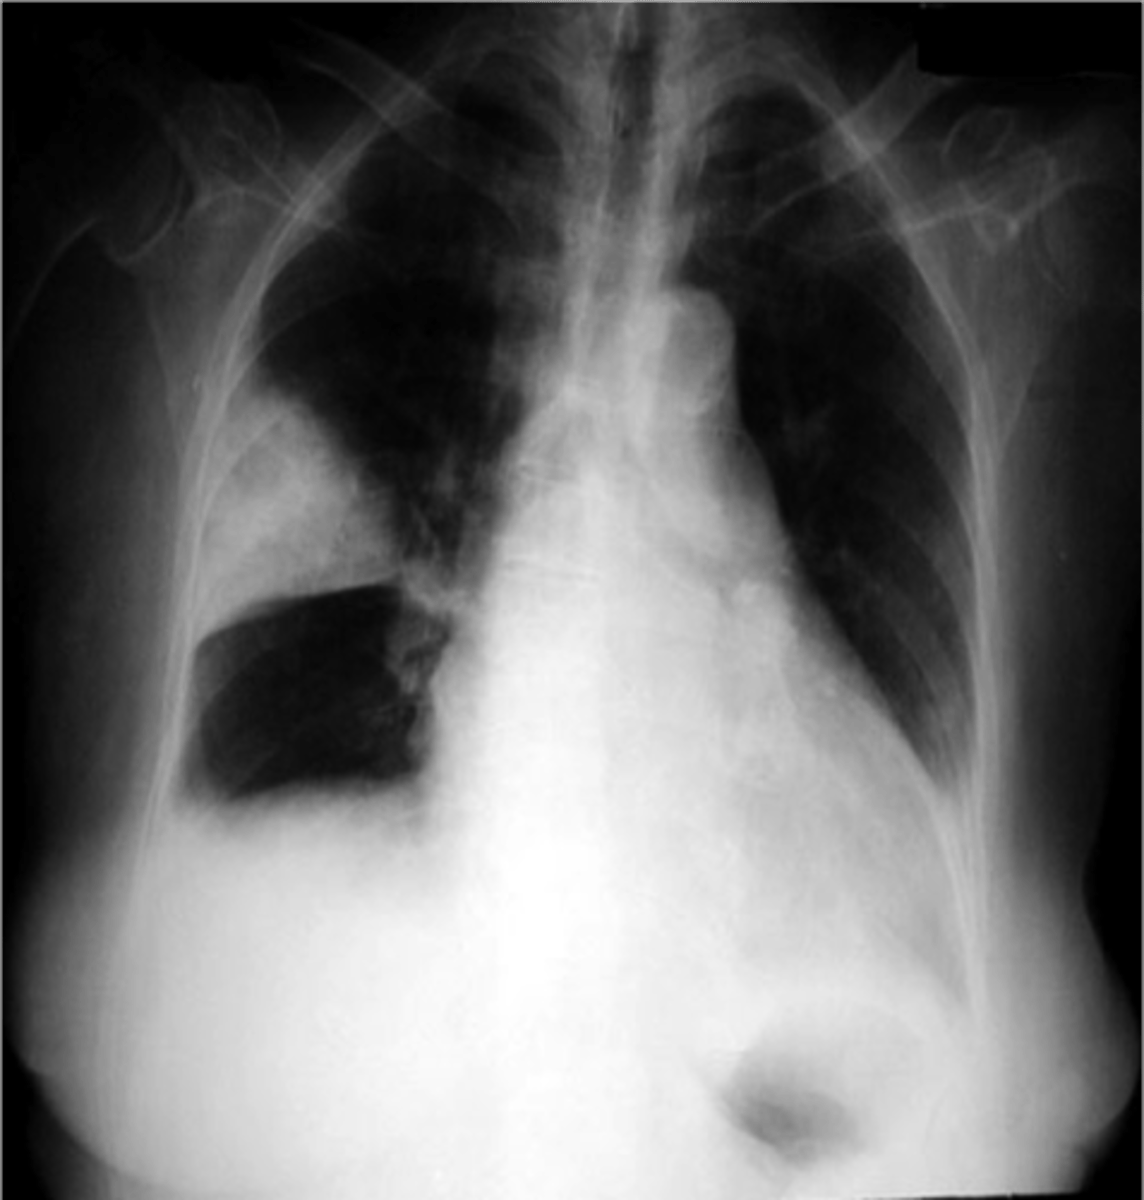

PE (hamptoms hump and westermark sign)

most often normal, but when not it looks like this

lack of vascular markings downstream of clot

westermark sign

pleural based opacities with convex medial margins, wedge-shaped, suggest infarct

hamptom hump